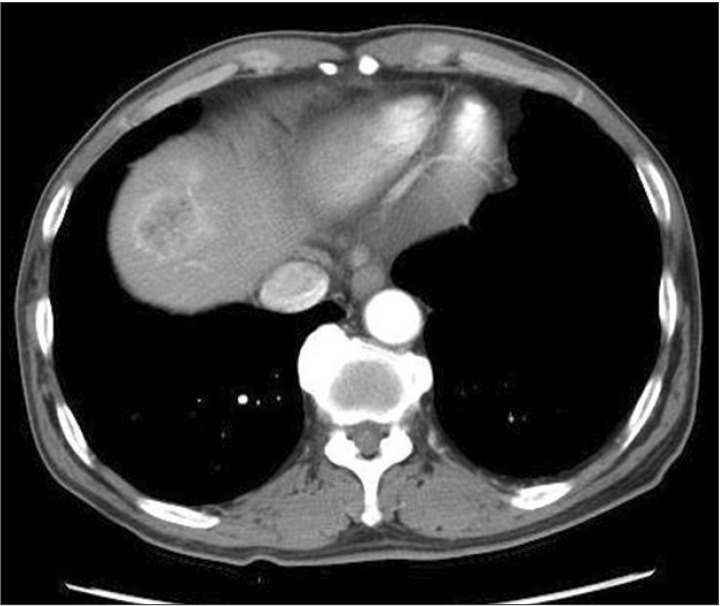

Computerized tomography in January 2008 (two months after the endoscopic submucosal dissection). A and B: Enhanced computerized tomography revealed multiple low density areas suggesting liver metastases (indicated by arrows).

An abdominopelvic computed tomography scan showing a 3.5-cm-mass in the liver that demonstrated strong enhancement following the intravenous administration of contrast material.